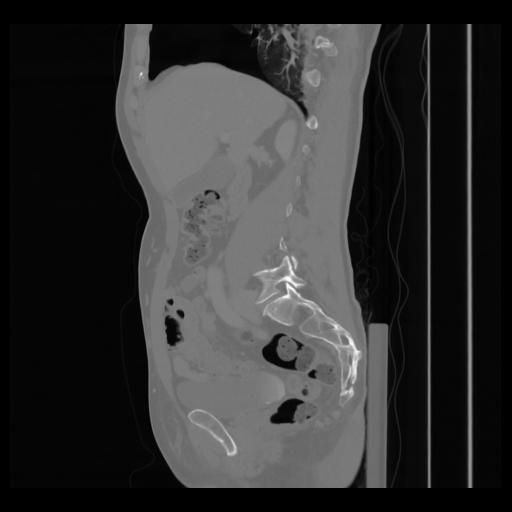

36 CUERPO,CE,Sagittal,3.000,CUERPO,Sagittal,